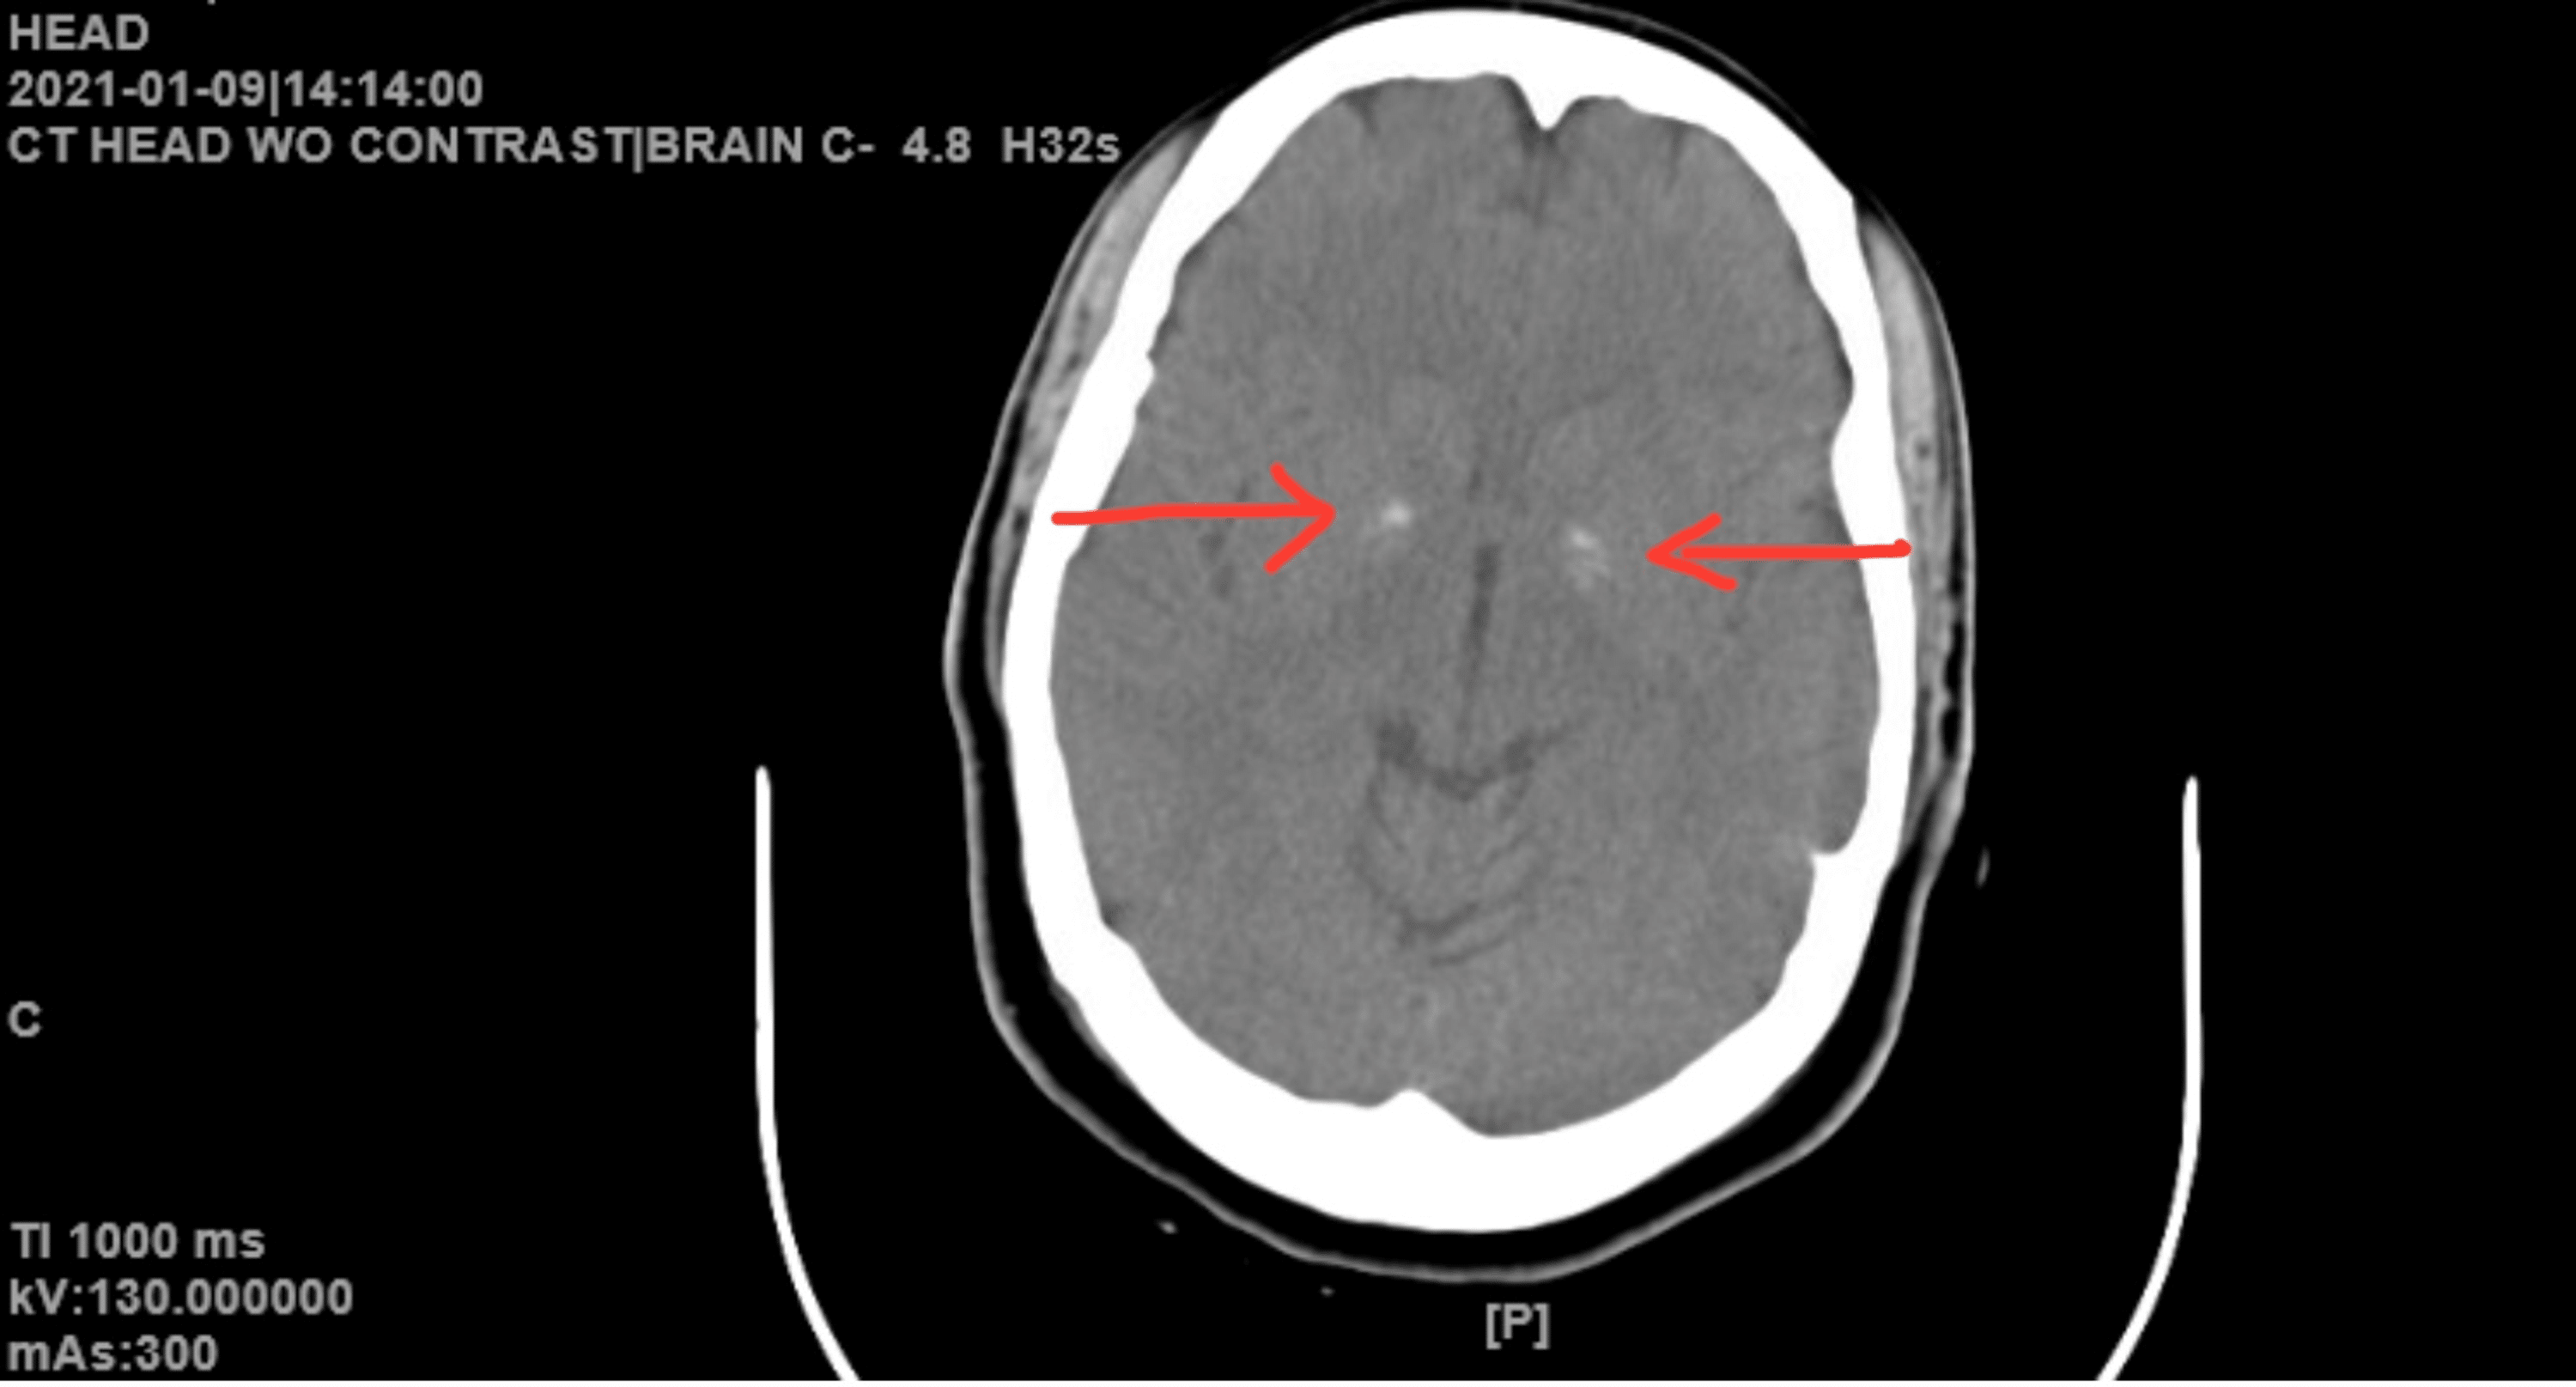

Basal Ganglia Calcification Causes . In this article, the authors discuss the etiology, pathogenesis, genetics, classification, and clinical manifestations of idiopathic basal ganglia calcification. Visualization of bilateral calcification of the basal ganglia on neuroimaging; Tremors, stiffness, or problems with coordination can sometimes be traced back to brain calcification, particularly when it affects. However, there are many causes of calcification: Basal ganglia calcification is when calcium deposits build up in parts of your brain. It can cause neurological and neuropsychiatric symptoms. Basal ganglia calcification is a rare condition where calcium builds up in your brain, usually in the basal ganglia. Common, globus pallidus most commonly affected. The diagnosis of pfbc relies on:

Brain computed tomography shows calcifications in the bilateral basal Basal Ganglia Calcification Causes The diagnosis of pfbc relies on: Basal ganglia calcification is a rare condition where calcium builds up in your brain, usually in the basal ganglia. It can cause neurological and neuropsychiatric symptoms. Visualization of bilateral calcification of the basal ganglia on neuroimaging; However, there are many causes of calcification: Common, globus pallidus most commonly affected. Tremors, stiffness, or problems with. Basal Ganglia Calcification Causes.

NCCT brain showing basal ganglia calcifications. Download Scientific Basal Ganglia Calcification Causes However, there are many causes of calcification: Tremors, stiffness, or problems with coordination can sometimes be traced back to brain calcification, particularly when it affects. Basal ganglia calcification is when calcium deposits build up in parts of your brain. In this article, the authors discuss the etiology, pathogenesis, genetics, classification, and clinical manifestations of idiopathic basal ganglia calcification. Common, globus. Basal Ganglia Calcification Causes.